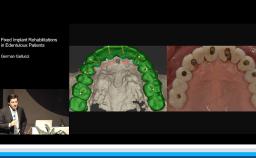

The lecture reviews the digital possibilities to design esthetics and thereby control the esthetic outcome in implant dentistry. The presentation begins with a discussion of the most frequently used criteria to define treatment success in implant dentistry. Clinical cases demonstrate how digital technologies allow planning in three dimensions for optimal esthetics. Practical methods to measure esthetic outcomes are also provided, based on four parameters: implant placement, soft tissue management, prosthetic considerations, and patient satisfaction.

- discuss the digital workflow in implant dentistry